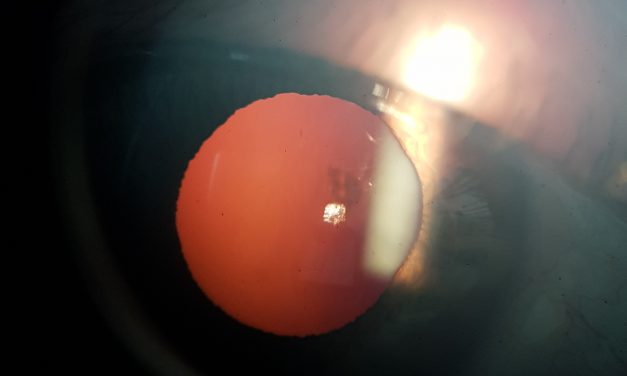

Per saperne di piùIn questa pagina pubblichiamo alcune immagini di cataratte Tutto quanto riguarda la cataratta, le...